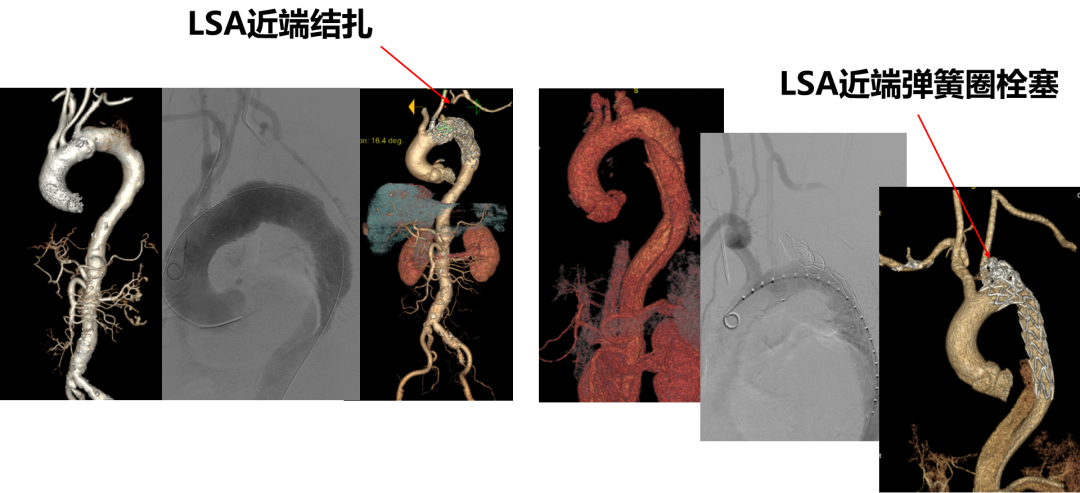

★ Case3:B型主动脉夹层,带分支支架重建LCCA+体外开窗技术重建LSA

★ Case4:主动脉弓部溃疡,带分支支架重建LCCA+平行支架IA+颈锁搭桥重建LSA

★ Case5:主动脉弓部溃疡,带分支支架重建LCCA+平行支架重建IA+原位开窗重建LSA